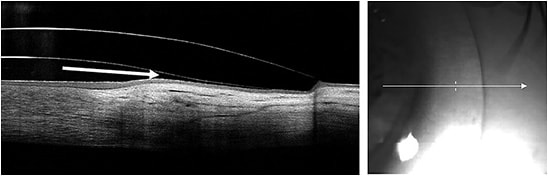

Optical Coherence Tomography (OCT) OCT has changed the way that eyecare practitioners monitor corneal conditions as well as the way that they optimize contact lens fits. For years now, scleral lens practitioners have been utilizing anterior segment OCT (AS-OCT) to measure central corneal clearance and to ensure limbal clearance. Additionally, the landing zone can be assessed utilizing AS-OCT to determine the appropriate fit (Figure 1).